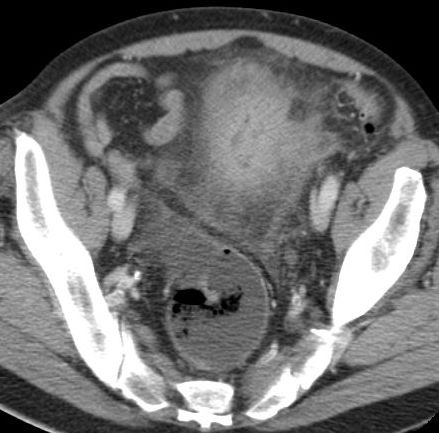

| Klinik | 72jähriger Mann mit kaffeesatzähnlichem, rötlichen Urin und 15kg Gewichtsabnahme. Stuhldurchmesser seit 4 Monaten vermindert.![]() |

![]() |